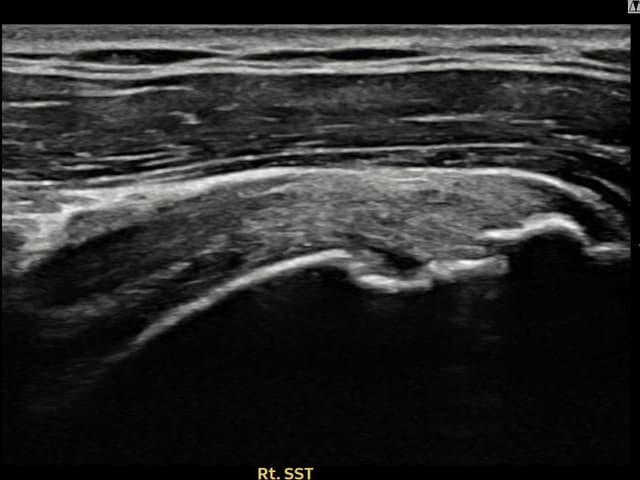

[촬영시기:23.09.01~23.11.03]

[어깨인대 축소봉합술] 우측 어깨 통증이 수개월간 지속되어 내원하셨습니다.